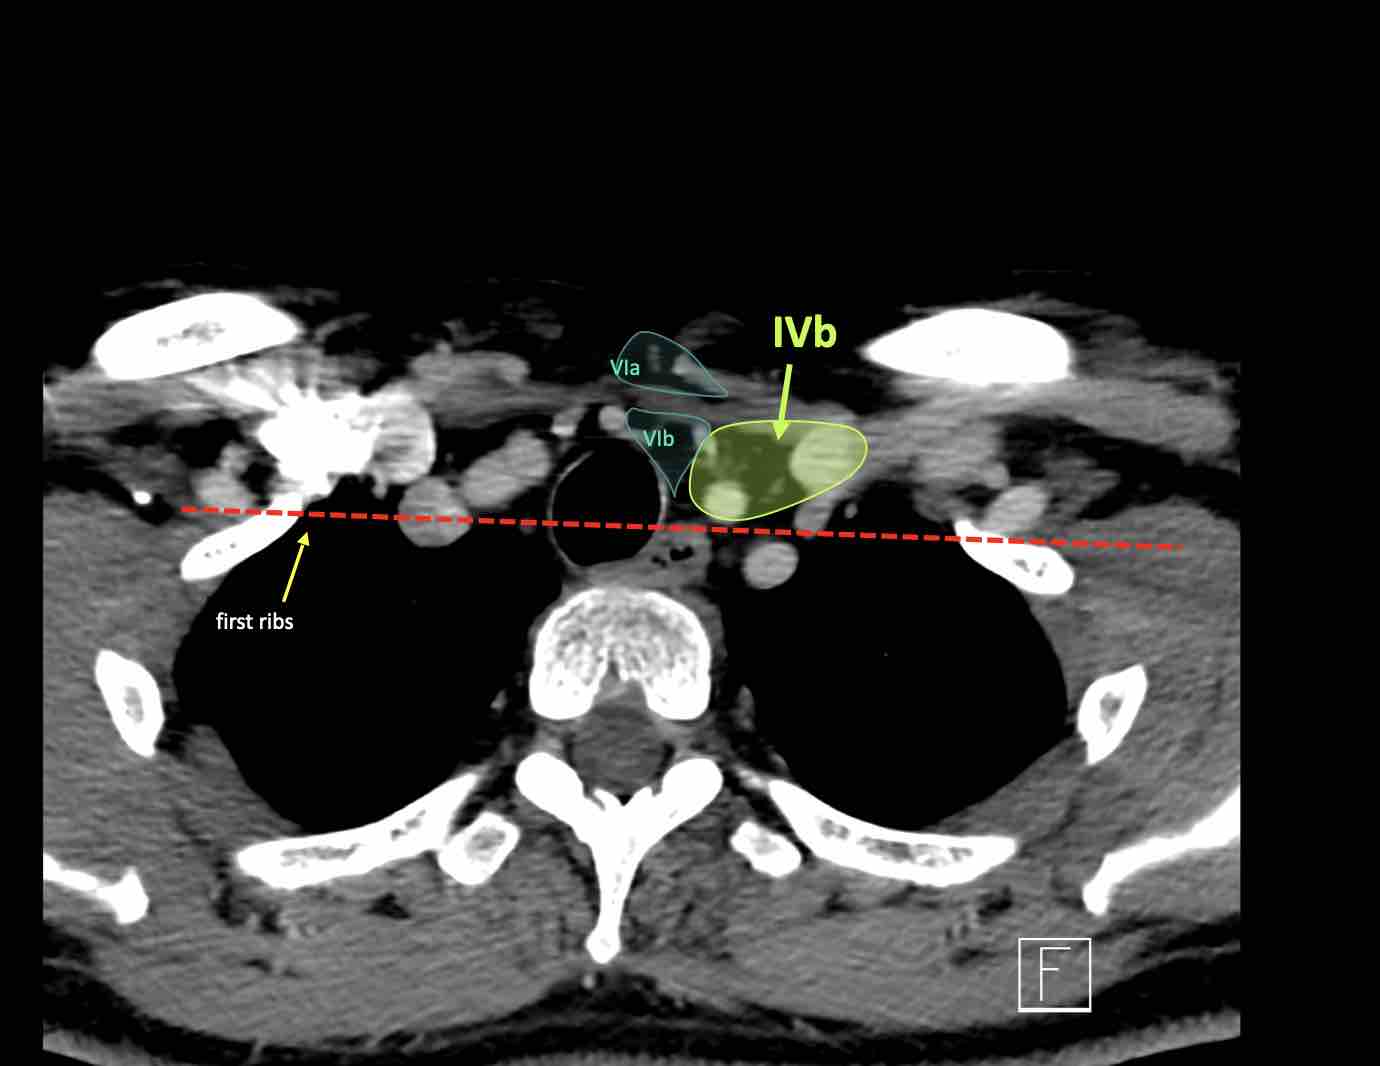

IV – Tĩnh mạch cảnh dưới và hố thượng đòn trong

Ranh giới giữa tầng IVa và IVb được xác định tùy ý tại vị trí 2 cm phía trên khớp ức đòn.

Tầng IVb

Các hạch này có nguy cơ chứa di căn từ các ung thư hạ hầu, thanh quản dưới thanh môn, khí quản, tuyến giáp và thực quản cổ.

VI – Cổ trước

Tầng này chứa các hạch tĩnh mạch cảnh trước nông (tầng VIa) và các hạch sâu hơn bao gồm hạch trước thanh quản, trước khí quản, cạnh khí quản và hạch thần kinh thanh quản quặt ngược (tầng VIb).